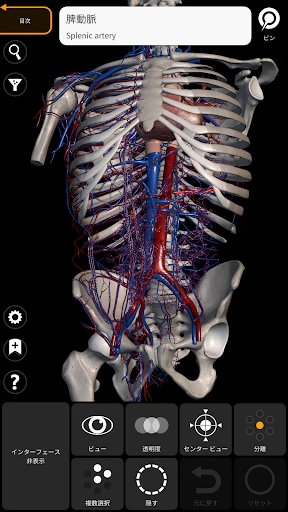

3Dアトラスの驚きの体験

皆さん、3Dで人体を探検したことはありますか?このアプリを使うと、まるで本物の標本を手に取っているかのように、人体の構造を詳細に観察できます。何よりも嬉しいのは、非常にリアルなグラフィックスです。3Dモデルはとても精密で、筋肉や骨、内臓の位置関係が一目瞭然です。

この「解剖学 - 3Dアトラス」、ただのビジュアルツールにとどまりません。かなり多くの情報が詰まっています。例えば、各部位の詳細な説明や、医学用語の解説も充実しているので、学習にはもってこいです。特に、試験勉強中の学生さんには非常に役立つことでしょう。

私のお気に入りの機能の一つは、特定の部位を選択すると、その部位に関する詳細な情報が表示されることです。これにより、単なるビジュアルだけでなく、知識を深めることができるのです。